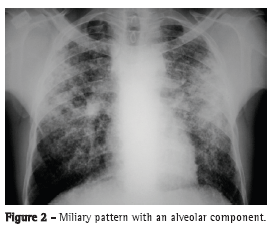

The most common radiological findings are reticular infiltrates and consolidation,(5,6,10,15,17) and cavitation can occur in 27-50% of cases.(6,10,16) Figures 1 to 4 show some of the main radiological patterns in this context.

The time from onset of symptoms to initiation of antituberculosis treatment has been reported to be over 30 days in 28.8-34.0% of cases.(6,17) The time from admission to initiation of appropriate treatment was evaluated in only one study, which reported a mean of 4.3 days. In that retrospective study, the time from admission to initiation of treatment was shorter in patients with miliary tuberculosis than in those with tuberculous pneumonia (2.8 ± 2.5 days vs. 5.0 ± 7.0 days; p = 0.048).(16) There can be a delay in diagnosis and, consequently, in initiation of treatment because it is difficult to differentiate tuberculous pneumonia from severe bacterial pneumonia on X-rays. Considering this difficulty in distinguishing the two pathologies, one study evaluated the differences between ICU patients with severe pneumonia and tuberculosis and those with severe pneumonia without tuberculosis in terms of their clinical and radiological characteristics. Symptom duration longer than two weeks and the presence of micronodules or a cavitary pattern on chest X-ray were significantly associated with active pulmonary tuberculosis.(20) In addition, a miliary pattern on chest X-ray can also be misinterpreted as congestive heart failure.(18)